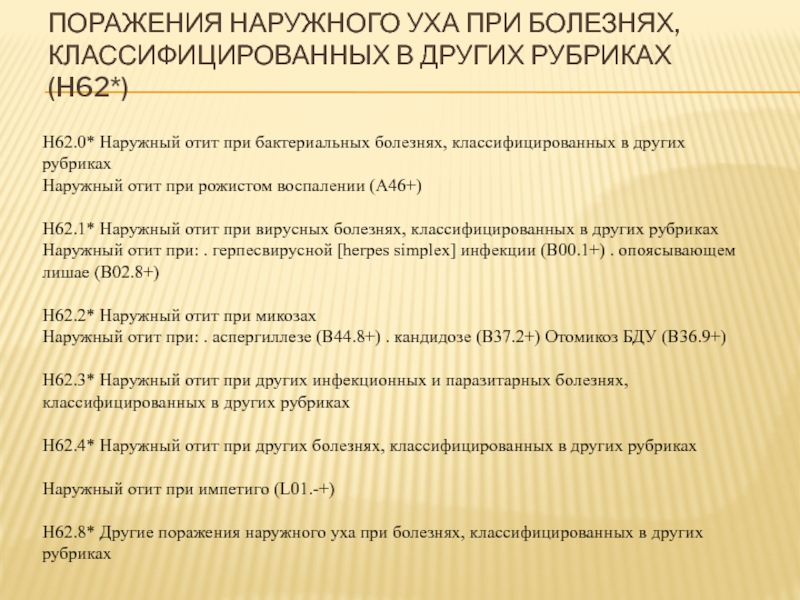

Код мкб 10 атерома головы

Код мкб 10 атерома головы 109 фото